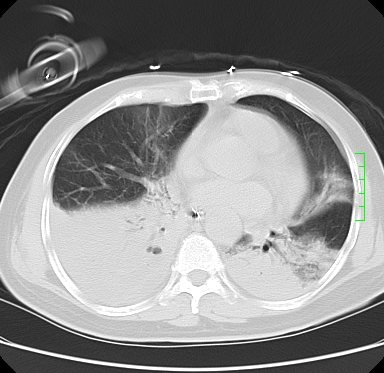

icu病人,几天都没明确诊断。m,76y,咳嗽、咳痰1周,伴气促,右胸痛入院,pe:t38.3c p135 r25 bp135/85。双肺可闻及大量湿罗音,心、腹未见明显异常。诊断:1心衰?2肺部感染?3冠心病?

9号平片

11号ct

双肺感染性病变,下叶膨胀不全,胸水,左室大。

1)两肺感染性病变(右肺下叶肺脓肿可能)。2)双侧胸腔积液,以右侧为甚。

ards,肺感染性病变,右下叶实变,双侧胸腔积液,右侧为著,叶间胸膜积液,右上肺陈旧性tb纤维灶,左室大。